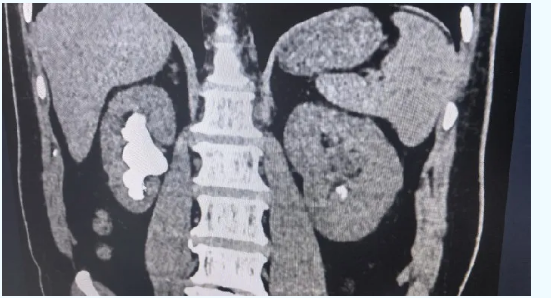

59岁的胡先生(化名)近一年来血压总是居高不下,最高一次达到230/100mmHg,还伴有胸闷、胸痛。他一度以为自己是心脑血管出了问题,住进洛阳白马医院内科后,医生详细检查发现——双侧肾脏都长满了结石,其中右肾有一颗直径约7厘米的鹿角形巨大结石,几乎占满了整个肾盂。

正是这颗大石头长期压迫肾脏、影响肾脏供血,导致身体不断分泌升高血压的物质,引发了顽固性肾血管性高血压。这种情况,光吃降压药效果往往不理想,只有把结石取出来,血压才有希望真正回落。